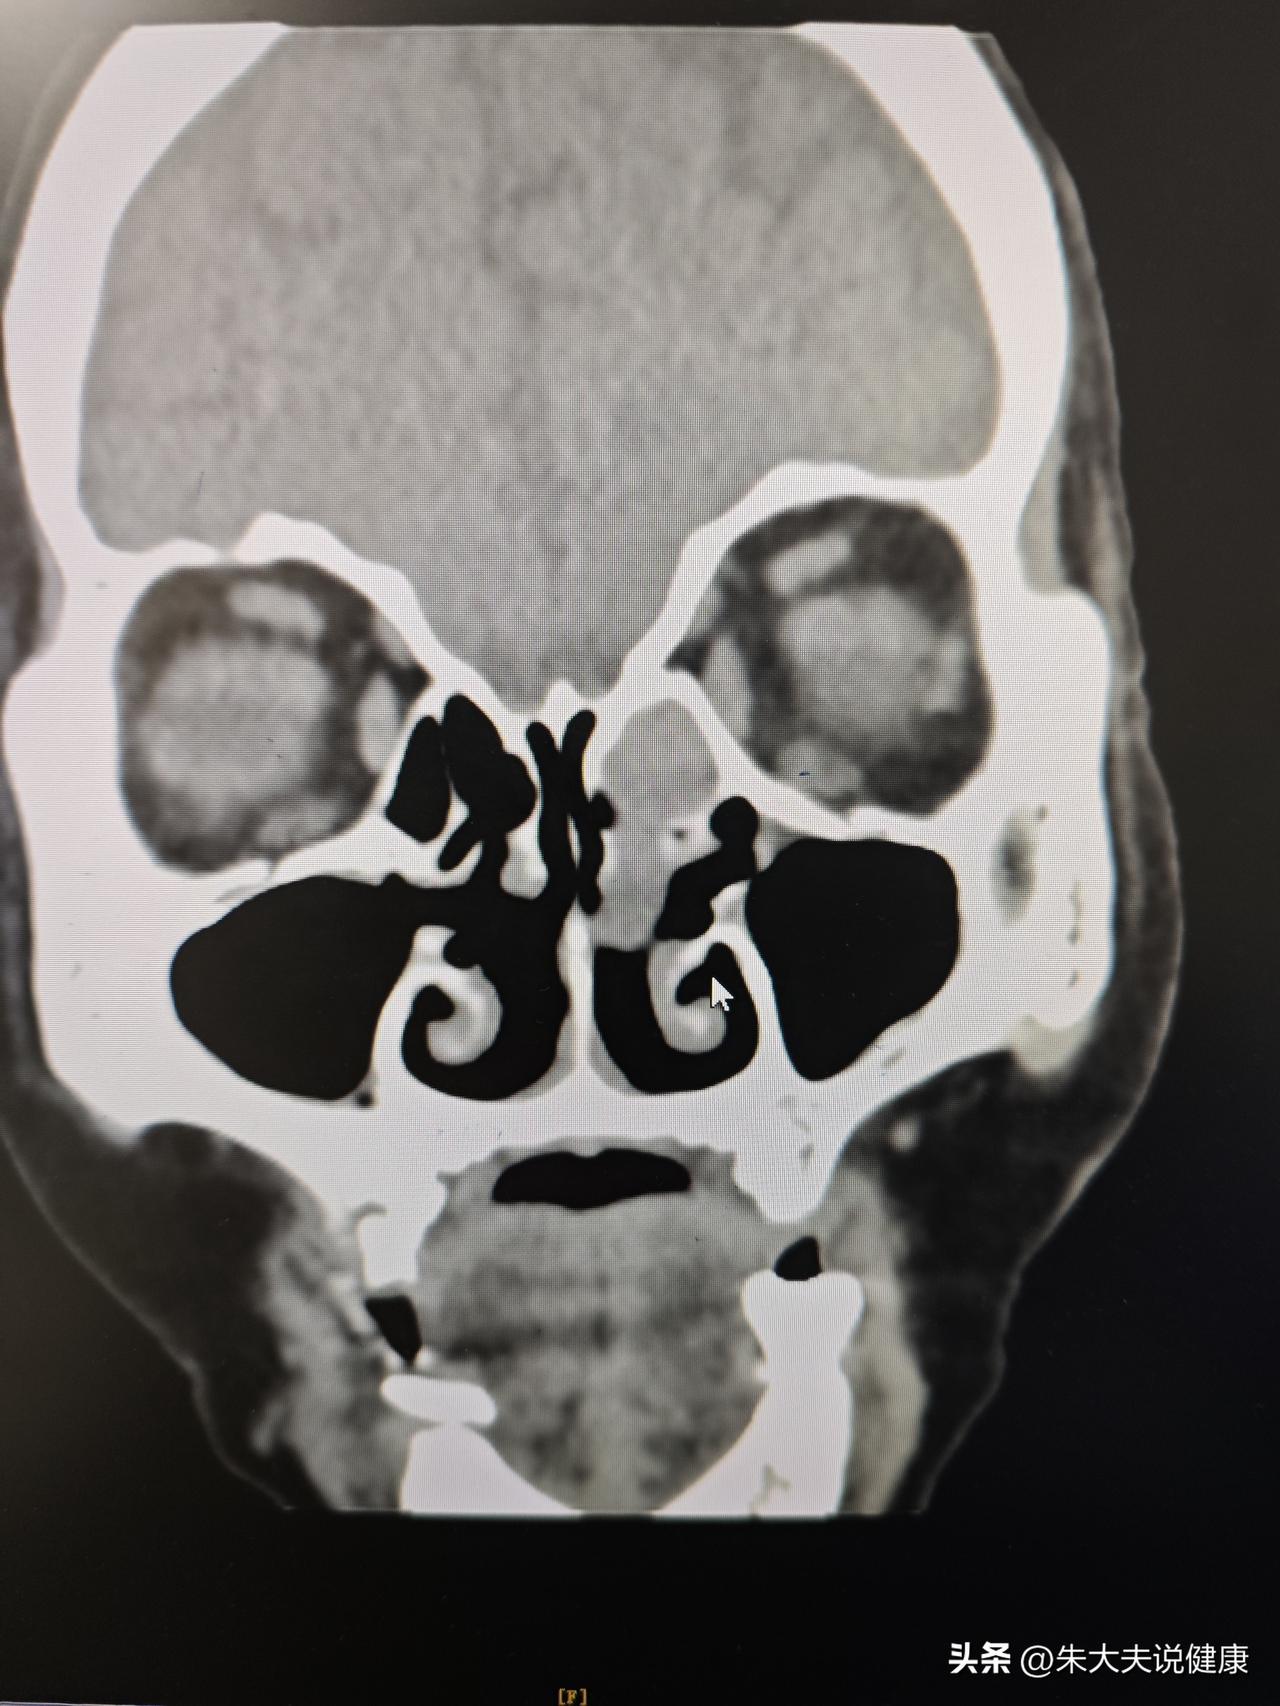

内翻性乳头状瘤,术后半年复查,预后良好

左侧鼻腔鼻窦内翻性乳头状瘤,术后三年复查,创面完全愈合,没有复发

鼻腔鼻窦内翻性乳头状瘤术后三年复查,创面完全愈合,没有复发